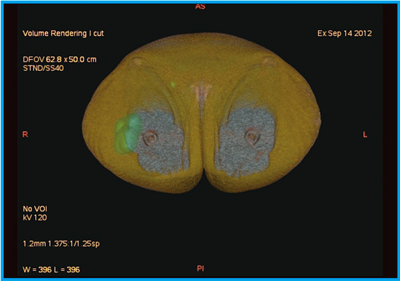

●症例3:右大腿悪性黒色腫原発巣術後のLymphoscintigraphy

当院では,乳腺領域以外でもセンチネルリンパ節検査を施行している。右大腿悪性黒色腫原発巣術後に対して,センチネルリンパ節の画像化を試みた。皮膚科医からは,深さ方向の情報の要望があり,皮膚面から掘り下げるようにして3D画像を表示することで,センチネルリンパ節の位置を確認することができる(図6)。さらに,脂肪を黄色に表示した横断像での観察も可能で,深さ方向の情報をより明確に得ることができる(図7)。CT画像でも小さなリンパ節が認められ,センチネルリンパ節を明瞭に同定することができた。

![]() 図6 症例3:右大腿悪性黒色腫原発巣術後のLymphoscintigraphy(a)とSPECT/CTフュージョン3D画像(b) |

![]() 図7 症例3:SPECT/CTフュージョン3D横断像 |